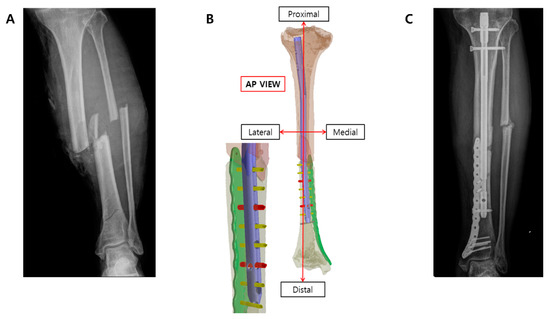

This study is among the first to explore the clinical applicability of pure titanium implants utilizing 3D printing technology. The results indicated that, out of 10 tibiae, nine had fracture plates that remained undamaged and were stably fixed. The findings from this study provide important insights into the clinical feasibility of utilizing 3D-printed pure titanium plates for distal tibia fractures. One of the primary advantages of employing 3D-printed pure titanium is its capacity to address anatomical mismatches between standard metal plates and patient-specific bone structures. This capability is particularly critical for distal tibia fractures, where the anatomical constraints of the medial tibia complicate proper fixation with conventional plates (Figure 5).

Figure 5.

Customized fracture plate designed to be combined using a tibia intramedullary nail. (A) A 68-year-old male presented to the emergency department after sustaining an injury to his left lower leg with a heavy load. On arrival, the patient was diagnosed with an open tibiofibular shaft fracture. The patient had a medical history of hypertension. An additional fracture line was identified in the distal tibia, raising concerns that adequate stability could not be achieved with an intramedullary nail alone. (B) Therefore, supplementary plating was considered. (C) After massive irrigation and confirmed wound stabilization, closed reduction and internal fixation with a tibia intramedullary (IM) nail and additional 3D-printed plate fixation were performed 1 week after the trauma. The soft tissue healed well without an additional coverage operation. Partial weight bearing was initiated 6 weeks post-operation. A successful union was achieved with an AOFAS score of 70.